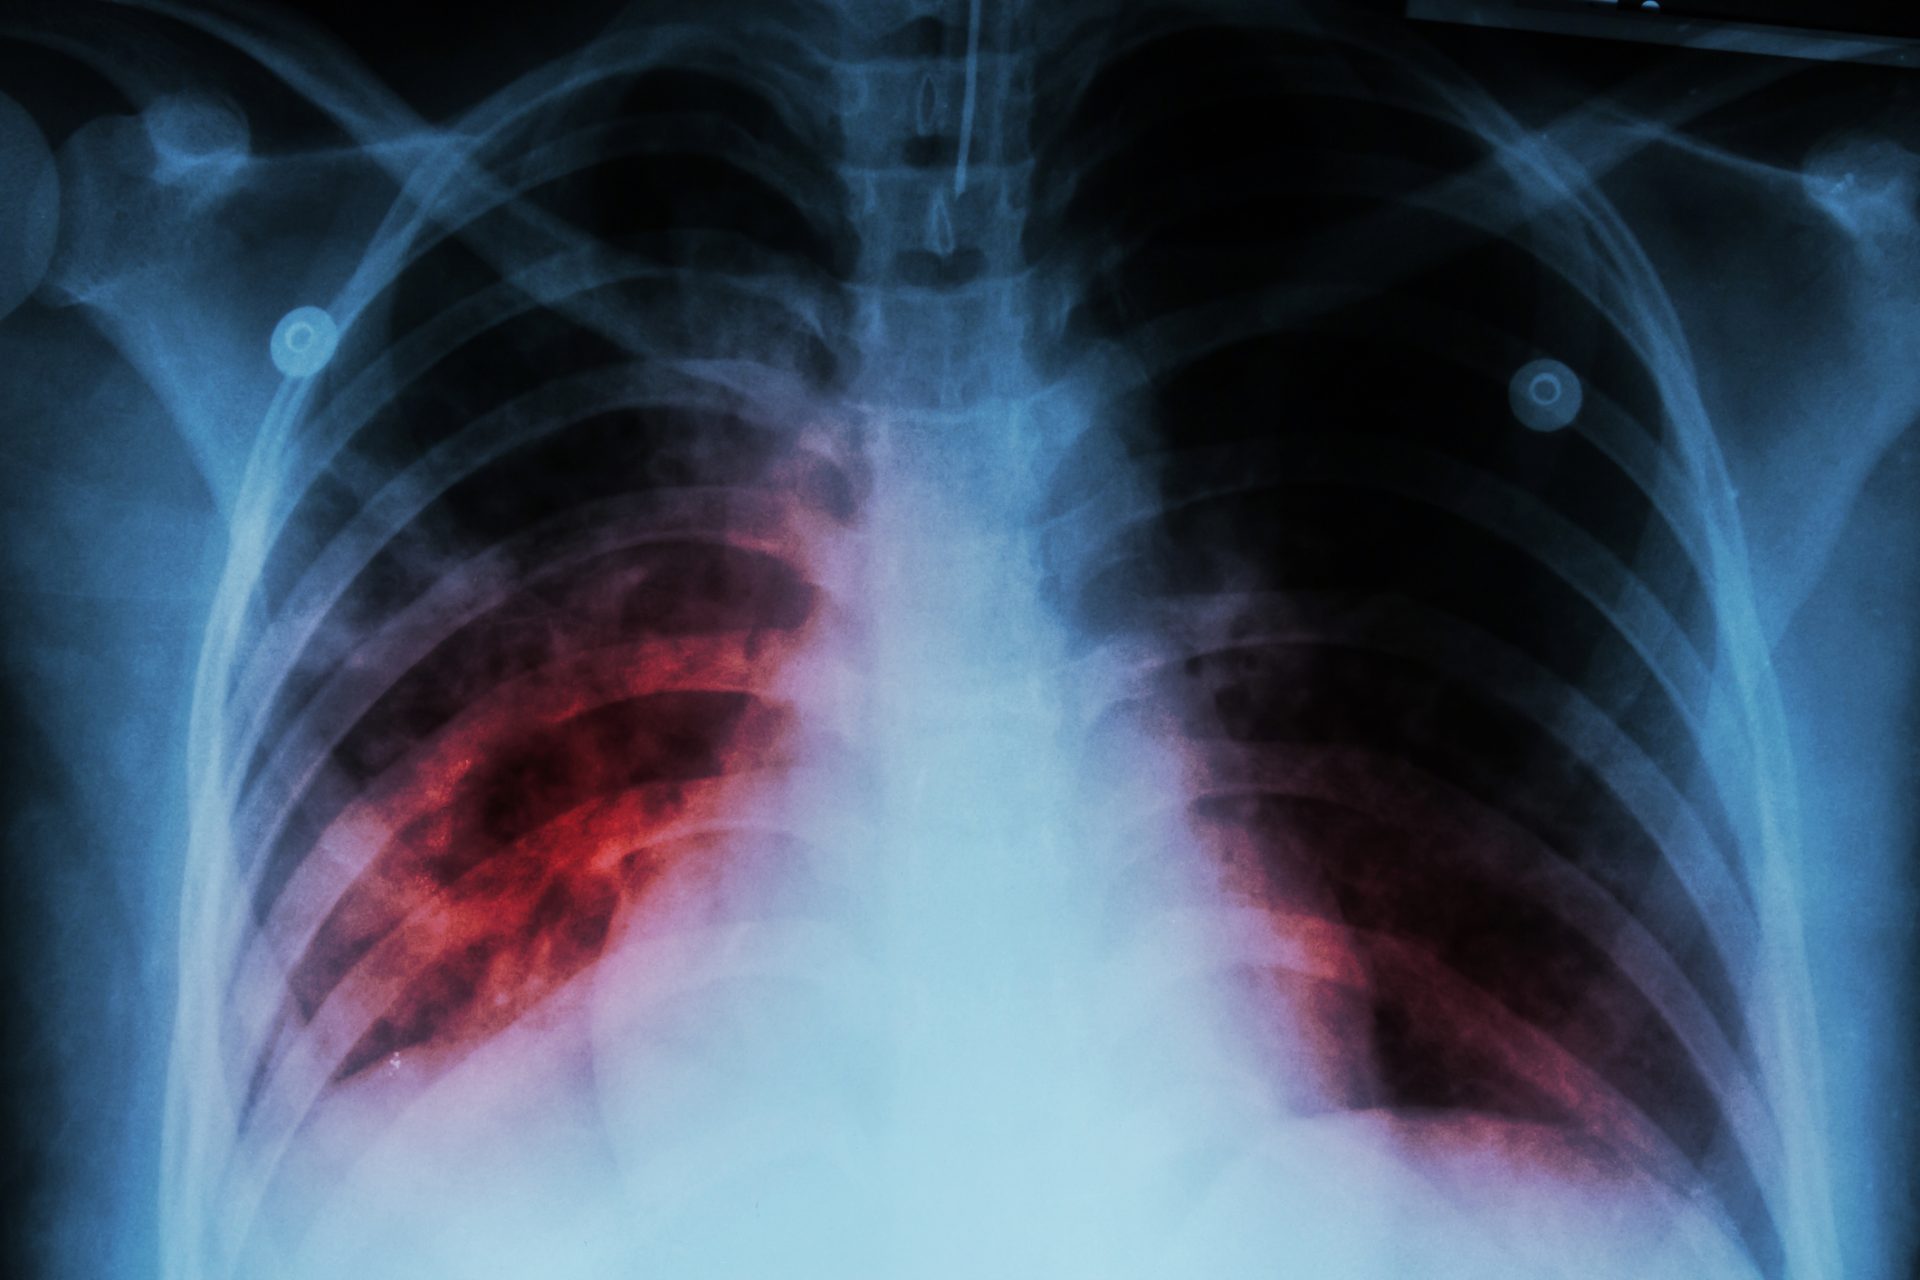

Foi detetado um caso de tuberculose pulmonar num hotel na região de Lisboa, anunciou esta quinta-feira a Direção-Geral da Saúde (DGS).

A tuberculose pulmonar transmite-se sobretudo pelo ar, quando uma pessoa com a doença liberta pequenas partículas infetadas ao tossir, falar ou espirrar, refere a DGS.

“Só a tuberculose que afeta as vias respiratórias é contagiosa. Quando é identificado um caso, as autoridades de saúde rastreiam os contactos próximos – pessoas que estiveram várias horas com o doente – para detetar eventuais infeções”, sublinha a entidade de saúde.